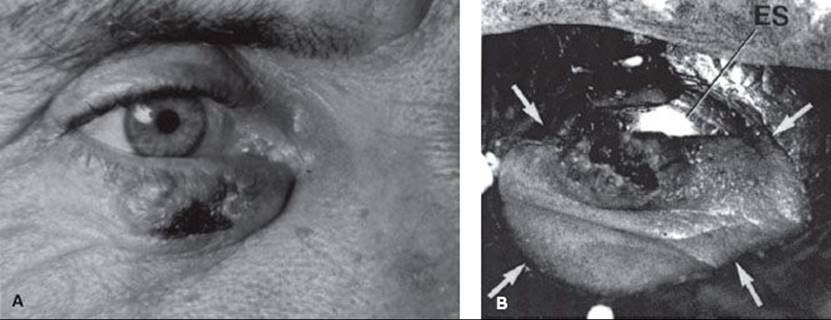

Before treatment with either electron-beam or orthovoltage x-rays, a customized lead mask is constructed to collimate the beam directly on the skin surface. A 1.0- to 1.5-cm margin is adequate for a well-defined T1 lesion treated with orthovoltage RT. An additional 1 cm is added to the margin when the electron beam is used to account for beam constriction. For larger and/or ill-defined tumors, a 2-cm margin is usually necessary. If the tumor is located near the eye, a gold-plated lead eye shield is placed directly on the anesthetized cornea to minimize the irradiation dose to underlying structures (Fig. 33.2). The dose beneath the eye shield is depicted for orthovoltage x-rays and electron beams of various energies in Table 33.4. Isodose distributions for the two techniques are shown in Figure 33.1; note that the dose distribution is better for orthovoltage RT than for electron beam, particularly if a lead mask is not used with the electron beam.

FIGURE 33.2. A: 1-cm é 1-cm basal cell carcinoma of the midportion of the lower lid. B: Treatment setup that was used to irradiate the patient. Arrows indicate the field edge. ES, eye shield.